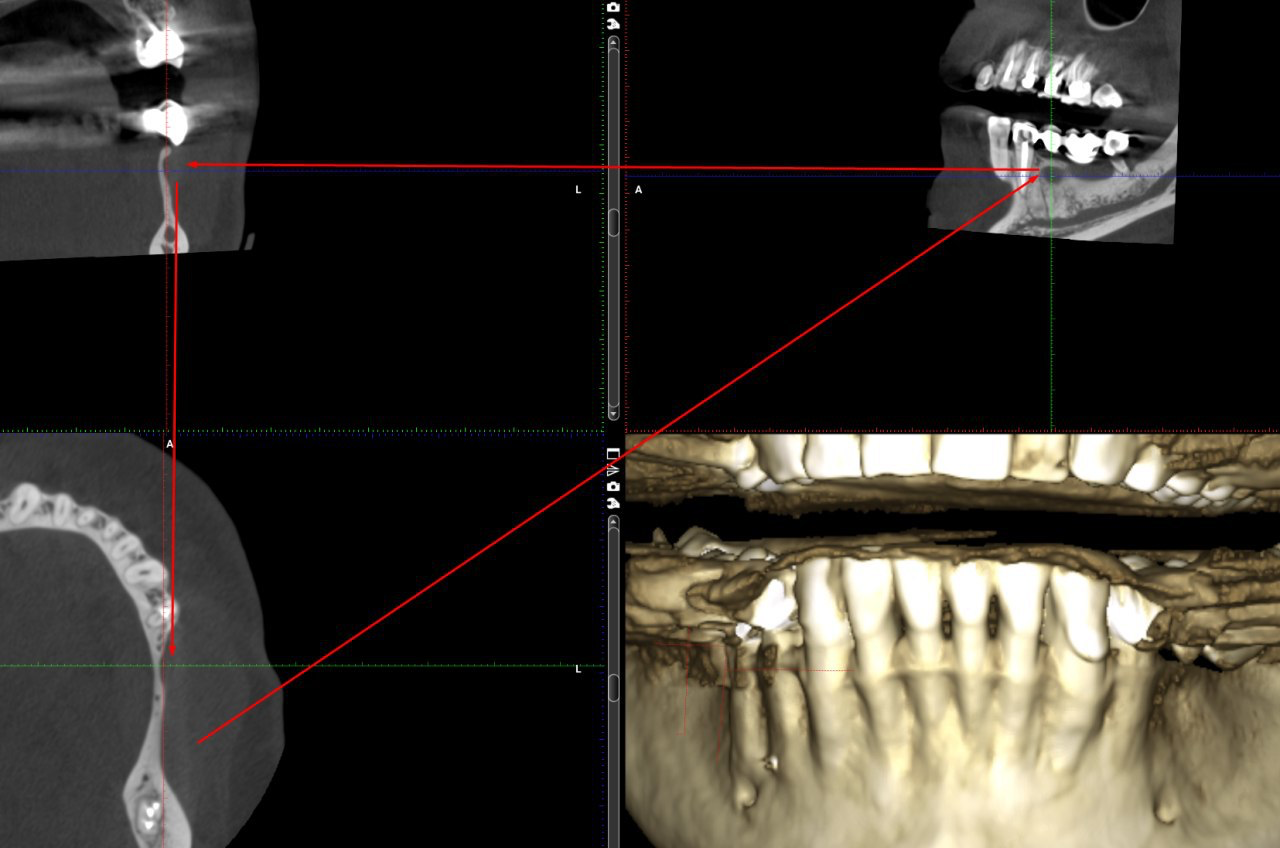

В результате сканирования нижней части головы пациента получается некий цилиндр, в котором есть разные органы, и навигацией в этом цилиндре врачи и занимаются.

Вот так выглядит эта навигация:

Но когда нам нужно добавить фото пациенту на аватарку или когда мы объясняем самому пациенту, что происходит, используется развёртка этого рулона в плоскость. Получается что-то вроде плоской карты мира вместо глобуса. Причём карта мира делается на глубине 13 миллиметров. Обычно как раз там находится всё самое интересное.

Итак, это 13-миллиметровый срез через толщу челюсти. Возможно, вы запоминаете людей в лица. Мы, стоматологи, запоминаем вас вот в такие 13-миллиметровые срезы.